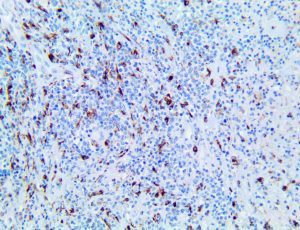

It is the ICU physician who is most likely to witness one of the deadliest manifestations of the abnormal immunological response, the cytokine storm syndrome (CSS). This response is also referred to by some as the cytokine release syndrome (CRS). CSS is characterized by continuous activation and expansion of macrophage and lymphocyte populations, which secrete large amounts of cytokines, causing the cytokine storm. This massive cytokine release is akin to hemophagocytic lymphohistiocytosis (HLH) disease, a syndrome characterized by initial unchecked and persistent activation of cytotoxic T lymphocytes and NK cells.

Clinical and laboratory manifestations of HLH include fever, enlarged liver and/or spleen, neurologic dysfunction, coagulopathy, liver dysfunction, cytopenias (i.e., low levels of erythrocytes, leukocytes, and/or platelets), hypertriglyceridemia, hyperferritinemia, hemophagocytosis, and eventually diminished NK cell activity as the immune system becomes progressively paralyzed. HLH can be familial (primary HLH) or secondary to another disease process (sHLH), such as rheumatic disease, in which it is referred to as macrophage activation syndrome (MAS, characterized by elevated ferritin).